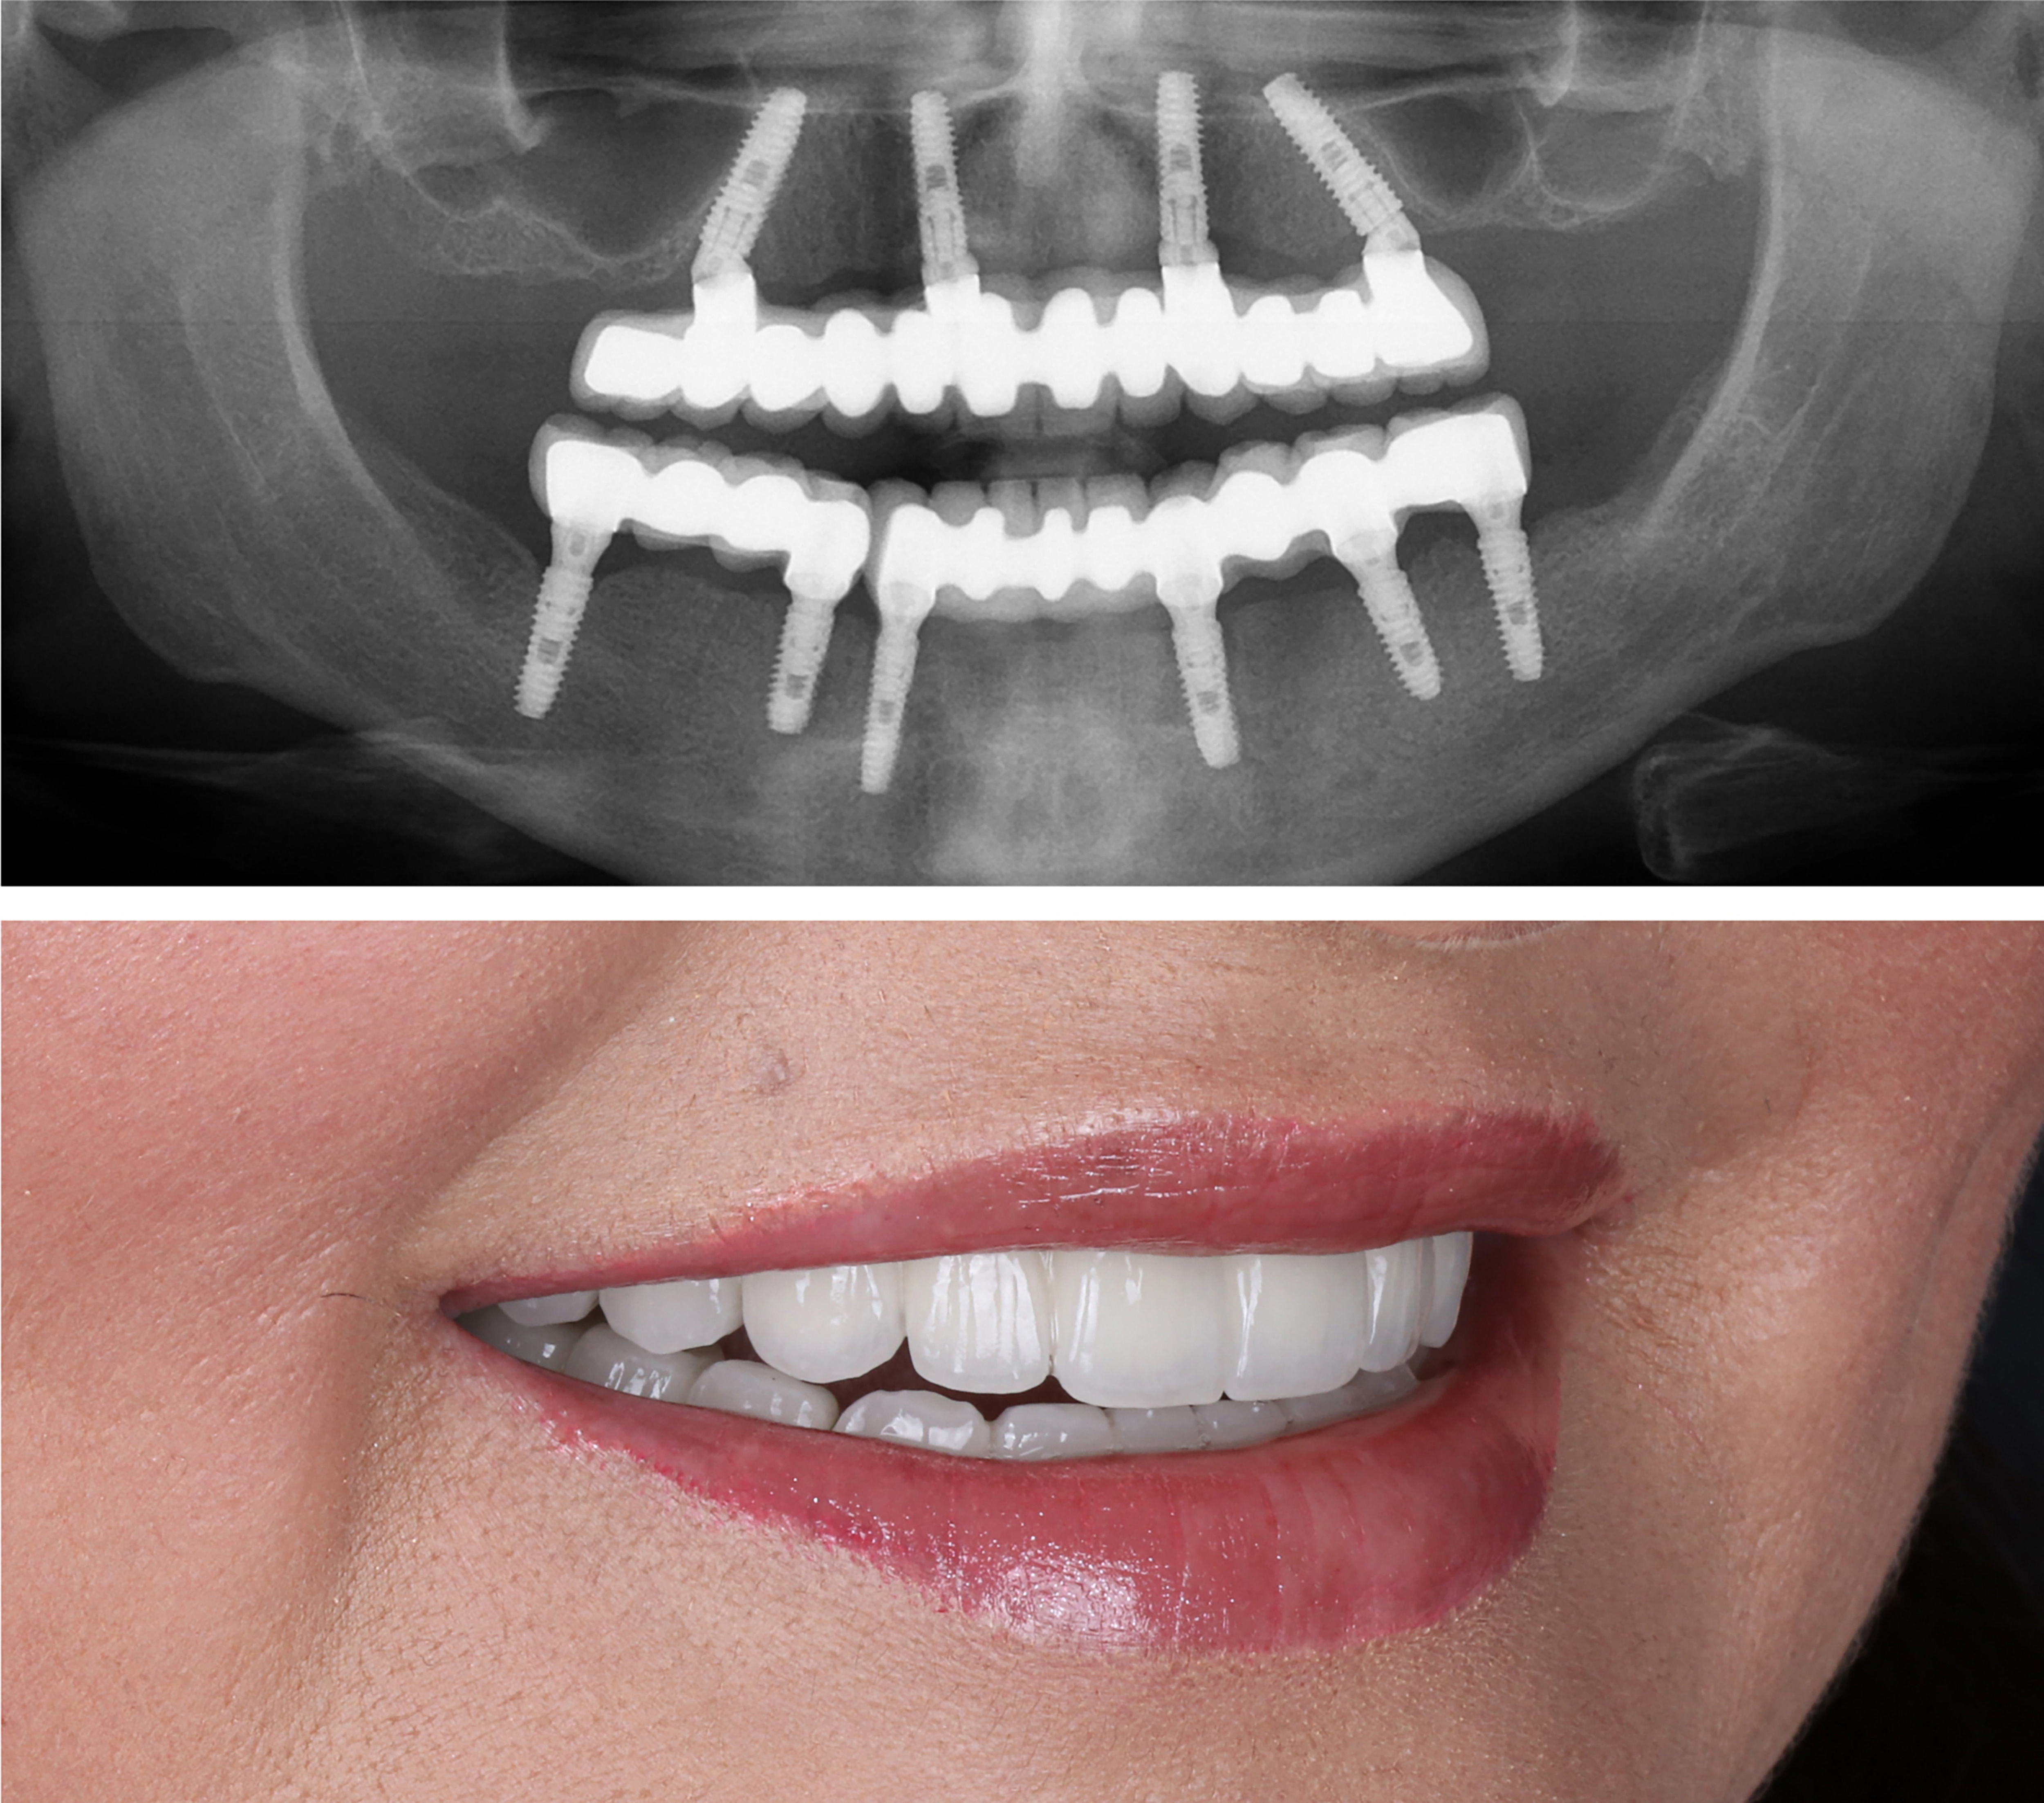

Example transformations achievable with dental implants

Includes everything from start to finish. No hidden fees.

Includes surgical placement of 4 to 8 implants.

In certain cases, extra pterygoid implants may be placed in the upper jaw by our oral surgeons to provide added strength and support for your zirconia teeth. ($6000 Value)

Before your final zirconia teeth are secured, you’ll wear a try-in set for two weeks. This ensures your comfort, bite, and smile look exactly right before moving forward.

Final ultra aesthetic zirconia fixed teeth.